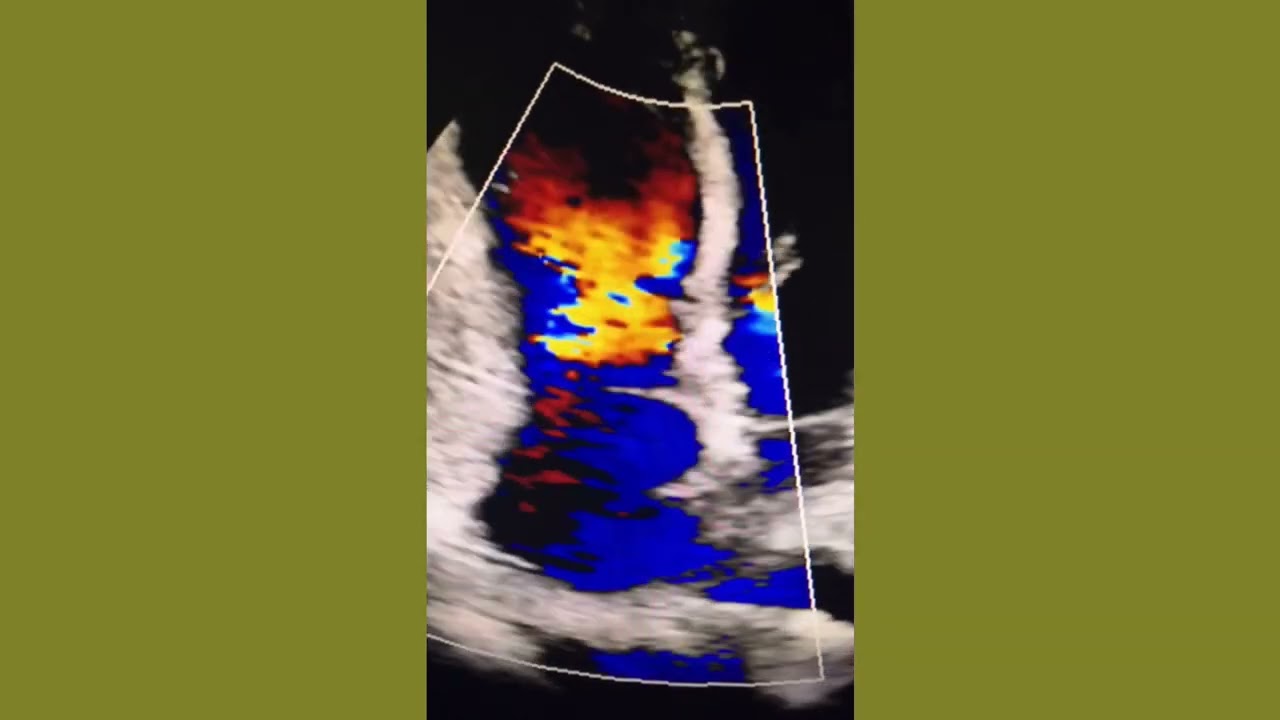

Patent Ductus Arteriosus (PDA)

Patent ductus arteriosus on echocardiography